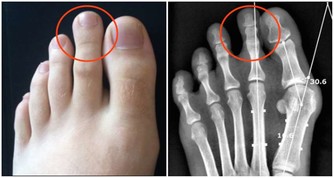

1.當腿肚子較大,腳腕特細的為家族史糖尿症狀,當糖尿症狀即將出現的時候腿部會出現酸,麻,脹的症三狀。

2.當腿肚子與腳腕一塊粗下來,說明家族史血糖症狀。

3.當腳腕特別粗的為家族史三高症狀,(高血壓,高血脂,高血糖)